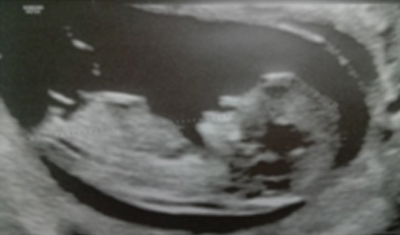

| 7-9ÁÖ | ÅÂ¾Æ ½ÉÀå ¹Úµ¿ È®ÀÎ |